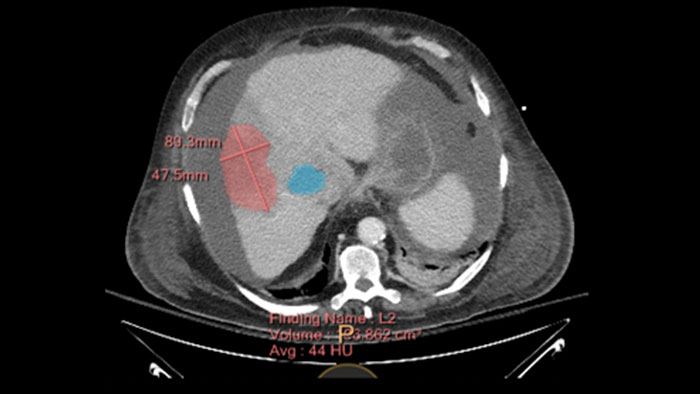

Inspection of tumors, as contrast enhanced, soft tissue oriented, and whole-body scans

Assists clinicians in viewing and evaluating CT images acquired on the IQon CT scanner for the inspection of tumors, as contrast enhanced, soft tissue oriented, and whole-body scans. It supports lesion viewing and analysis based on different spectral data types such as iodine density maps or virtual non-contrast-enhanced images.

Semi-automatic tumor quantification

This semi-automated 3D (Volumetric) tumor response assessment tool, based on EASL (European Association for the Study of the Liver) criteria incorporates functional information from contrast-enhanced scans.